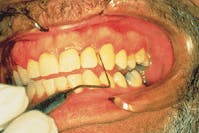

The patient was a 40-year-old male who had a positive medical history for high blood pressure, diabetes, and allergies. He was being medicated with chlorine for gout. The clinical exams revealed extremely broken-down dentition, as well as Type IV, severe periodontitis. The periodontal probing indicated a 12 mm infrabony defect on the mesial-facial of #6 (see Figure 6).

Dr. Robert Barr diagnosed and planned treatment for the case. One of the authors provided the therapy under direct supervision in compliance with the dental practice act in California. The treatment plan called for scaling and root planing with laser curettage, which would be followed by bone graft surgery.

In order to treat the entire oral cavity, the patient received 10 hours of laser therapy for the soft tissue. The first full hour was devoted to tooth #6. After microultrasonics and scaling with light root planing, the laser curettage was set to the following parameters with a Pulsed Nd:YAG: 1064 nm - 300 micron fiber; 30mJ, 60Hz, 1.8W. Each site was treated for 40 to 60 seconds and followed by microultrasonics.

The parameters for the bacterial decontamination were: 100mJ, 20Hz, 2.0W. Each site was treated for 30 seconds, followed by the delivery of antimicrobial irrigant with microultrasonics.

The first hour of therapy was devoted to tooth #6 (see Figure 7). During subsequent weekly appointments, the tooth was treated again following the decontamination parameters. A local anesthetic was used at the site during the first four appointments. After each treatment with the laser, the site was irrigated with the antimicrobial agent. The laser fiber and ultrasonic tip were measured shorter at each "re-treat" so that new attachment was not disturbed.

Figure 6 A 12mm infrabony defect was noted on the mesial-facial of tooth #6.

Figure 7 Laser curettage is performed on tooth #6.